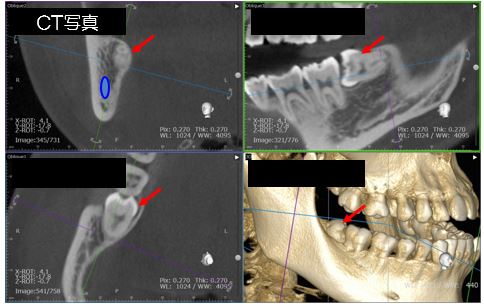

親知らずの歯根は顎骨の中を通る神経と近いことが多く、CT写真で位置を確認しながら抜歯を行っています。